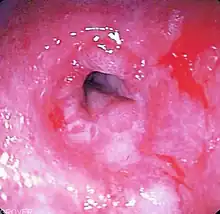

Barrett's esophagus

GERD may lead to Barrett's esophagus, a type of intestinal metaplasia,[20] which is in turn a precursor condition for esophageal cancer. The risk of progression from Barrett's to dysplasia is uncertain, but is estimated at 20% of cases.[30] Due to the risk of chronic heartburn progressing to Barrett's, EGD every five years is recommended for people with chronic heartburn, or who take drugs for chronic GERD.[31]

Endoscopy

Endoscopy, the examination of the stomach with a fibre-optic scope, is not routinely needed if the case is typical and responds to treatment.[42] It is recommended when people either do not respond well to treatment or have alarm symptoms, including dysphagia, anemia, blood in the stool (detected chemically), wheezing, weight loss, or voice changes.[42] Some physicians advocate either once-in-a-lifetime or 5- to 10-yearly endoscopy for people with longstanding GERD, to evaluate the possible presence of dysplasia or Barrett's esophagus.[45]

Biopsies performed during gastroscopy may show:

- Goblet cell intestinal metaplasia or Barrett's esophagus